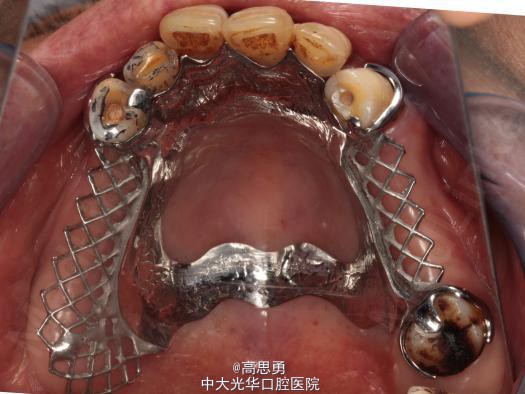

5、试戴支架 检查支架的就位、固位可,无翘动,调HE,抛光,用蜡堤取颌位关系,上颌架,排牙,比色C4。

6、试排牙 检查义齿的就位、固位可,无翘动,观察人工牙的咬合状况,尖窝接触良好,正中颌位能重复,患者无诉不适,面容自然,外观满意。送加工厂充胶制作最终修复体。

7、试戴 检查义齿的就位、固位可,无翘动,咬合关系正确,利用咬合纸检查,上下颌尖窝接触均匀全面,抛光,患者表示满意,嘱注意事项,定期复诊。

病历发表的很认真,很详细,双侧或者单侧游离缺失,传统三臂卡修复对基牙扭力很大,楼主这方面考虑的很周到,在游离端缺失都选择了RPA或者RPI卡环,改变义齿支持模式...查看全部